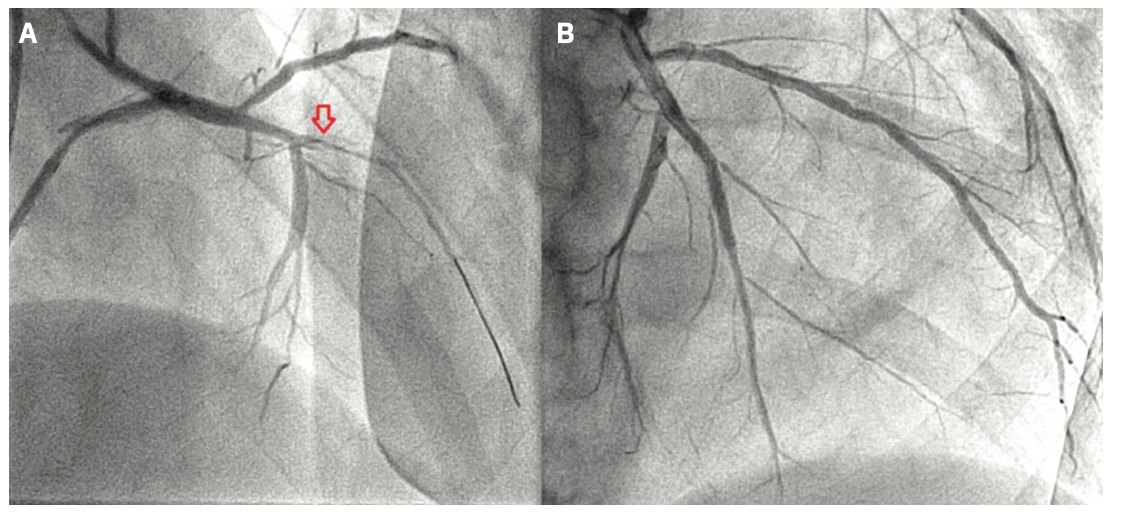

A 65-year-old male presented with a few days of productive cough, progressive fatigue, worsening scrotal edema, and high-grade fever. His past medical history included essential hypertension, tobacco abuse, ischemic cardiomyopathy with a left ventricular ejection fraction (LVEF) of 20%, and severe multivessel coronary artery disease (CAD) involving the left main (LM) (80%), mid left anterior descending artery (LAD) (100%), and distal right coronary artery (RCA) (90%). Vital signs at presentation were notable for hypotension and sinus tachycardia. Physical exam showed 2+ pitting edema of the lower extremities, significant scrotal edema, and inspiratory and expiratory wheezes on auscultation. Laboratory test results were notable for troponin elevation of 0.12 ng/mL and BNP of 7722 pg/mL. Creatinine was elevated at 1.74 mg/dL, which was above the patient’s baseline. An electrocardiogram (EKG) showed inferior Q waves, widespread T wave abnormalities, a right bundle branch block, and a left posterior fascicular block (Figure 1). The chest x-ray showed cardiomegaly without pulmonary infiltrates/consolidation. An echocardiogram showed a severely enlarged left ventricle with a left ventricular ejection fraction of 15%-20%. During his hospital stay, the patient developed cardiogenic shock requiring short-term inotropic support with dobutamine. After stabilization, the patient underwent a coronary angiogram, which showed progression of his CAD with a 90% distal LM stenosis, mid-LAD chronic total occlusion (CTO), and a 99% distal RCA lesion. In the past, the patient had elected not to pursue invasive management and was treated only medically. This time, the patient was willing to consider any treatment option, so cardiothoracic surgery was consulted. The patient was not found to be a good candidate for surgical revascularization. Before discharge, the patient underwent successful percutaneous coronary intervention (PCI) of the RCA with drug-eluting stent (DES) placement. Two weeks later, he presented for staged PCI of the LAD CTO. For the procedure, right radial access was utilized. Dual access was not obtained due to the absence of significant right-to-left collaterals. The LM ostium was engaged with a 6 French Launcher Extra Backup (EBU) 3.5 guide catheter (Medtronic). Initially, the procedure proceeded according to the plan. We were able to cross the LAD CTO without significant difficulties using a Prowater .014-inch, 180 cm coronary guide wire (Abbott Vascular) (Figure 2A). Unfortunately, we were unable to advance further interventional equipment into the lesion. Eventually, we managed to partially insert a semi-compliant balloon into the proximal end of the stenotic area. At this point, with two-thirds of the Sprinter Legend Rx 1.5 mm x 6 mm balloon (Medtronic) still proximal to the lesion, we elected to go forward with the technique of controlled balloon explosion (Figure 2B). Eventually, balloon rupture (Figure 2C) occurred at a pressure of 20 atmospheres. The following angiogram showed a dissection in the LAD, an expected finding with this technique (Figure 3A). After the successful lesion modification, we advanced a 2.0 mm x 20 mm Euphora Rx balloon (Medtronic) for the purpose of post dilatation. Subsequently, a 2.5 mm x 34 mm Resolute Onyx (Medtronic) drug-eluting stent was successfully placed (Figure 3B). The remainder of the procedure was uneventful. For his LM disease, the patient successfully underwent staged high-risk PCI. A repeat echocardiogram after 3 months showed an improved EF at 25%-30%.